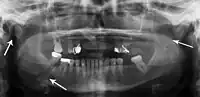

Panoramic radiograph of a simple mandible fracture of the right mandibular body, minimally displaced. Note that the teeth to the left of the fracture do not touch